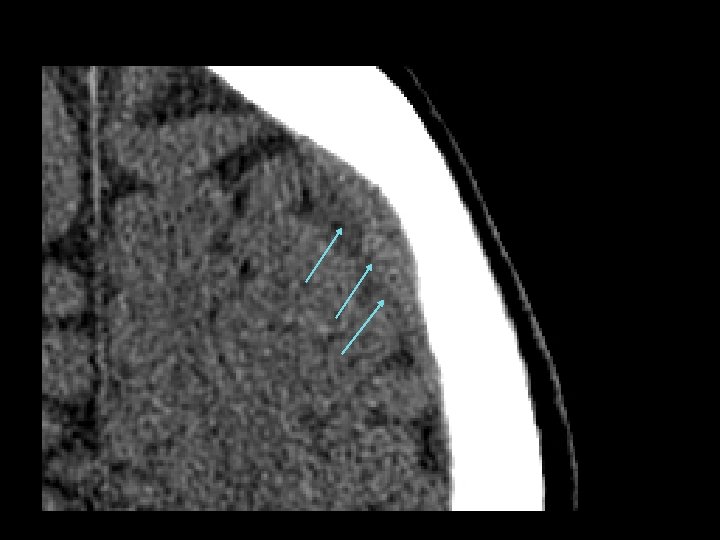

Vỡ xương sọ • Nhiều dạng: – Nứt, lún, rạn nền sọ • Cắt lớp dạng cửa sổ xương • Tổn thương não ở điểm vỡ xương sọ là rất quan trọng • Dường nứt sọ: – Nếu nứt sọ kín, có thể chỉ quan sát theo dõi

Vỡ xương sọ • Vỡ nền sọ: – Thường liên quan đến xương thái dương – Chẩn đoán lâm sàng (CT thường bỏ sót chẩn đoán) • Dấu hiệu đeo kính râm, chảy máu tai, dấu hiệu Battle (tụ máu sau tai), dò nước não tủy qua mũi • Lún sọ: – Phẫu thuật nâng lún: • nếu lớn hơn độ rộng của sọ hoặc • > 5 mm